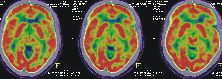

3、PET/CT神经系统显像

·脑恶性肿瘤的恶性程度分级、边界确定,治疗后坏死与复发的鉴别

·癫痫患者的诊断及病灶术前定位

·脑血管病变的早期诊断和脑功能评价